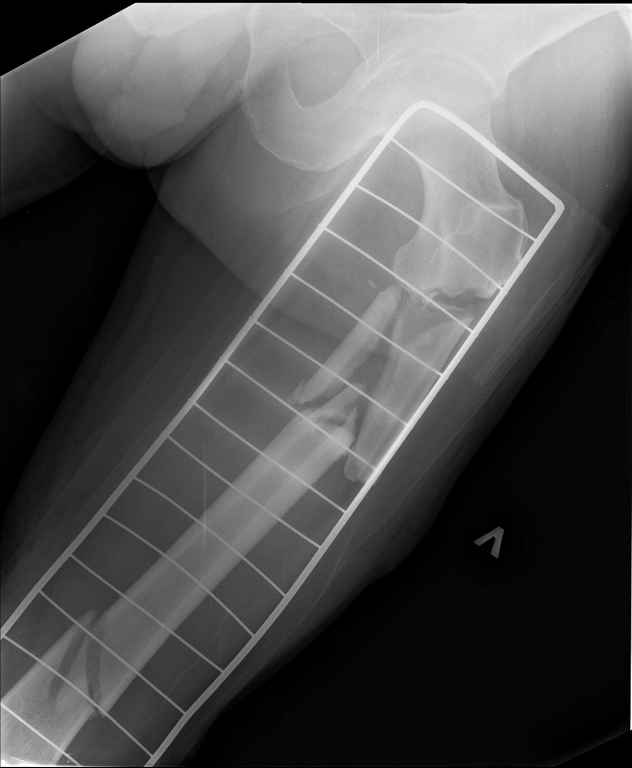

Ds: ТСТ. ЗЧМТ. СГМ. ЗТГК. О/фрагментарный перелом левого бедра. З/оскольчатый перелом с\3 левого плеча. Перелом левого локтевого отростка. З/перелом наружного мыщелка б/берцовой кости в/3 м/берцовой кости левой голени. при поступлении, ПХО раны левого бедра( рана 1х1см по наружной поверхности бедра в с/3) налажено скелетное вытяжение , и гипсовая лонгета на левую в/конечность. Находился в реанимации. 17.02.11 был прооперирован: БИОС левого плеча, о/синтез левого локтевого отростка по Веберу, БИОС левого бедра (длинная версия Fi-Can Sanatmetal диаметр 10мм), мыщелок голени трогать не стали.при остеосинтезе бедра возникли трудности при закрытй репозиции перелома в н/3, в связи с чем решили открыться внизу , отрепонировали без особого труда и выполнили блокирование во фронтальной плоскости 3-мя винтами + 1 винт спереди гвоздя (промазал). Убрал костодержатель, все нормально, контроль ЭОПом стояние отломков нормальное, зашились. На контрольной R-мме на утро выявлено вторичное смещение дистального отломка. Левая нога по сравнению со здоровой удлиннена до 2,5см( это за счет вальгусной установки гвоздя в проксимальном отделе, боялся свалиться на варус). Теперь думаем как поправить положение отломков в н/3, и зафиксировать так чтобы не съехало. Наше предложение расшиться в н/3 бедра, разблокироваться, перелом отрепонировать вновь и установить 1или 2отклоняющих винта в сагитальной плоскости, затем заблокироваться во фронтальной плоскости снова. Помогите советом, как выйти достойно из сложившейся ситуации. Заранее спасибо.